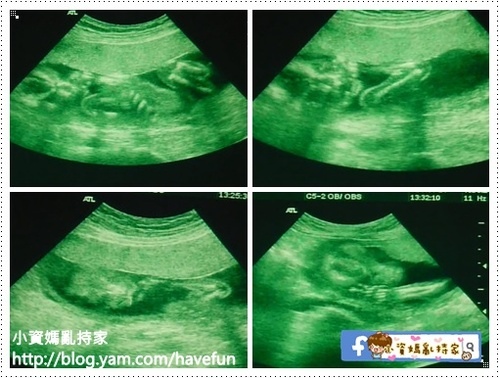

這次也難得能夠讓我看拉拉看得久一點

看到他一會吸拇指,一會咬手指裝性感,一下又枕手睡覺,花招好多

這次的超音波除了檢查頭圍腹圍之外,也檢查了胃、肺、腎臟、膀胱等器官

其中好幾度超音波師陷入靜默,不斷的在拉拉頭頂掃來掃去

原本我很擔心是否有甚麼問題,原來是因為胎盤擋住了,超音波師看不清楚拉拉的小腦跟側腦

但超音波師還是非常有耐心的花了十幾分鐘慢慢地掃,中間幾度手痠休息,但還是堅持幫我看到了